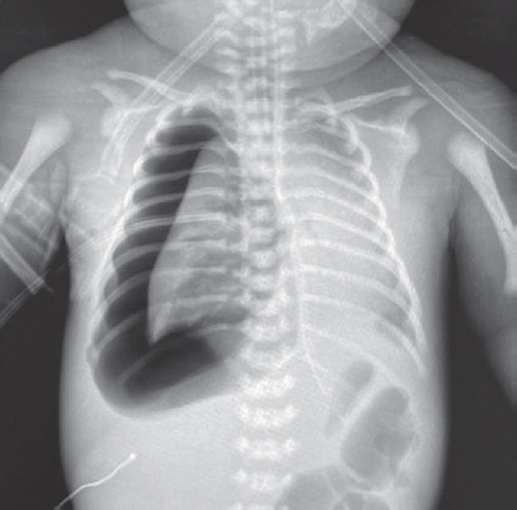

На контрольной рентгенограмме, выполненной на вторые сутки жизни (после введения сурфактанта), сохраняются признаки тяжелого РДС, осложнившегося правосторонним напряженным пневмотораксом (рис. 2), в связи с чем по экстренным показаниям было выполнено дренирование плевральной полости.

Рис. 2. Рентгенограмма органов грудной клетки новорожденного после введения сурфактанта

Fig. 2. Chest X-ray of newborn after surfactant administration